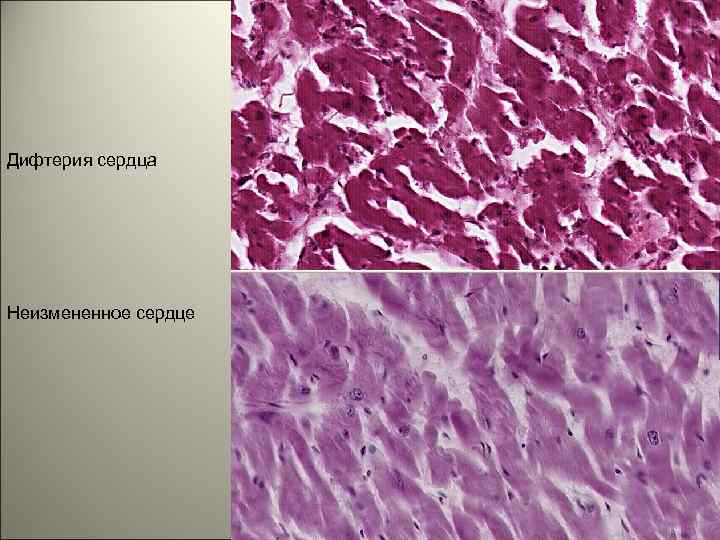

• При отсутствии какого-либо из основных компонентов: 1) фибринозное воспаление, 2) локализация в гортани, 3) возбудитель- бацилла Леффлера; круп не считается истинным, несмотря на клинические проявления в виде удушья, осиплости. Такие явления могут возникать при отёке гортани (ложном крупе). 125

Дифтерия сердца Неизмененное сердце 128